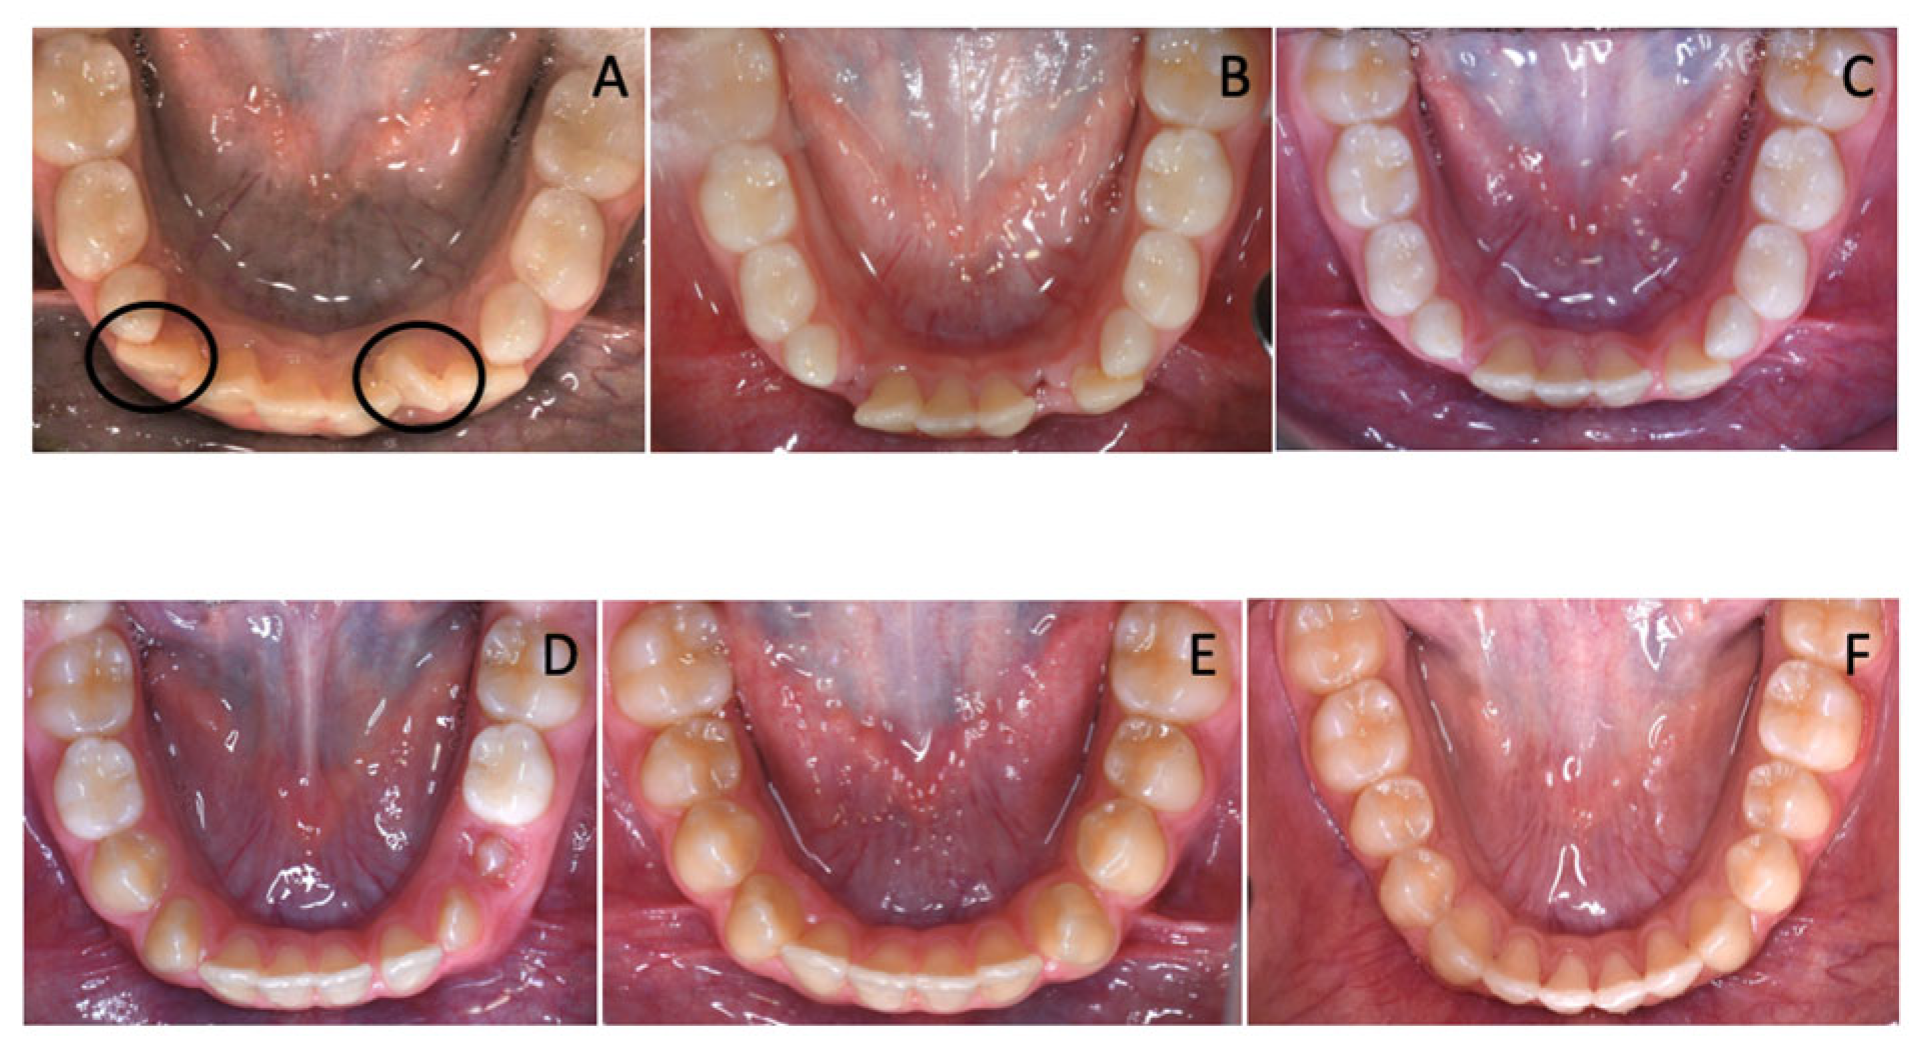

Figure 7. (A) The supplemental teeth selected for extractions circled in black; (BE) Spontaneous lower incisor alignment after supplemental teeth extractions and (F) refinement of lower incisor alignment after multibracket therapy.

The treatment plan comprised the extraction of supplemental teeth in order to correct the lower crowding and allow regular arch development. Considering the very similar morphology of the 6 incisors, the supplemental teeth that should have been extracted were selected according to their position. In the observed case, the incisor on the left side was extracted because it was the most rotated and farthest one from the arch perimeter. Therefore, it would have been unlikely for it to undergo a spontaneous realignment that would have more easily occurred for the other elements. Alongside, the other supernumerary tooth was selected for extraction, depending on its distal position on the right side that would have been an obstacle for the eruption of fourth quadrant dental elements (Figure 2).

Clinically speaking, the early diagnosis of supplemental teeth is essential to optimize treatment outcomes and prevent complications. Supernumerary teeth may cause crowding, impaction, or delayed eruption of adjacent permanent teeth [18,19,20,21,22]. In many cases, timely extraction of the supernumerary teeth can help avoid these issues and restore dental alignment [20,23,24,25]. Spontaneous eruption of permanent teeth occurs in most of the cases in which supernumerary teeth have been removed [26,27]. However, if supernumerary teeth have already erupted, adjacent elements might spontaneously align after the extraction of supernumerary teeth, without the aid of orthodontic devices [28]. In these cases, when no additional orthodontic treatment is indicated, the ideal approach is to monitor the progress during dental exchange, thanks to the support of photographic records and documented clinical changes. In the case herein, the use of multibracket appliance or other devices during the first phase of treatment to promote the lower incisor alignment would have represented an overtreatment, given the fact that teeth can spontaneously move towards extractive spaces [29,30,31,32,33] (Figure 7A–E). As a matter of fact, the second phase of treatment with multibracket appliance required a very slight refinement of the alignment already achieved thanks to physiological repositioning of the mandibular incisors in the space gained (Figure 7F).